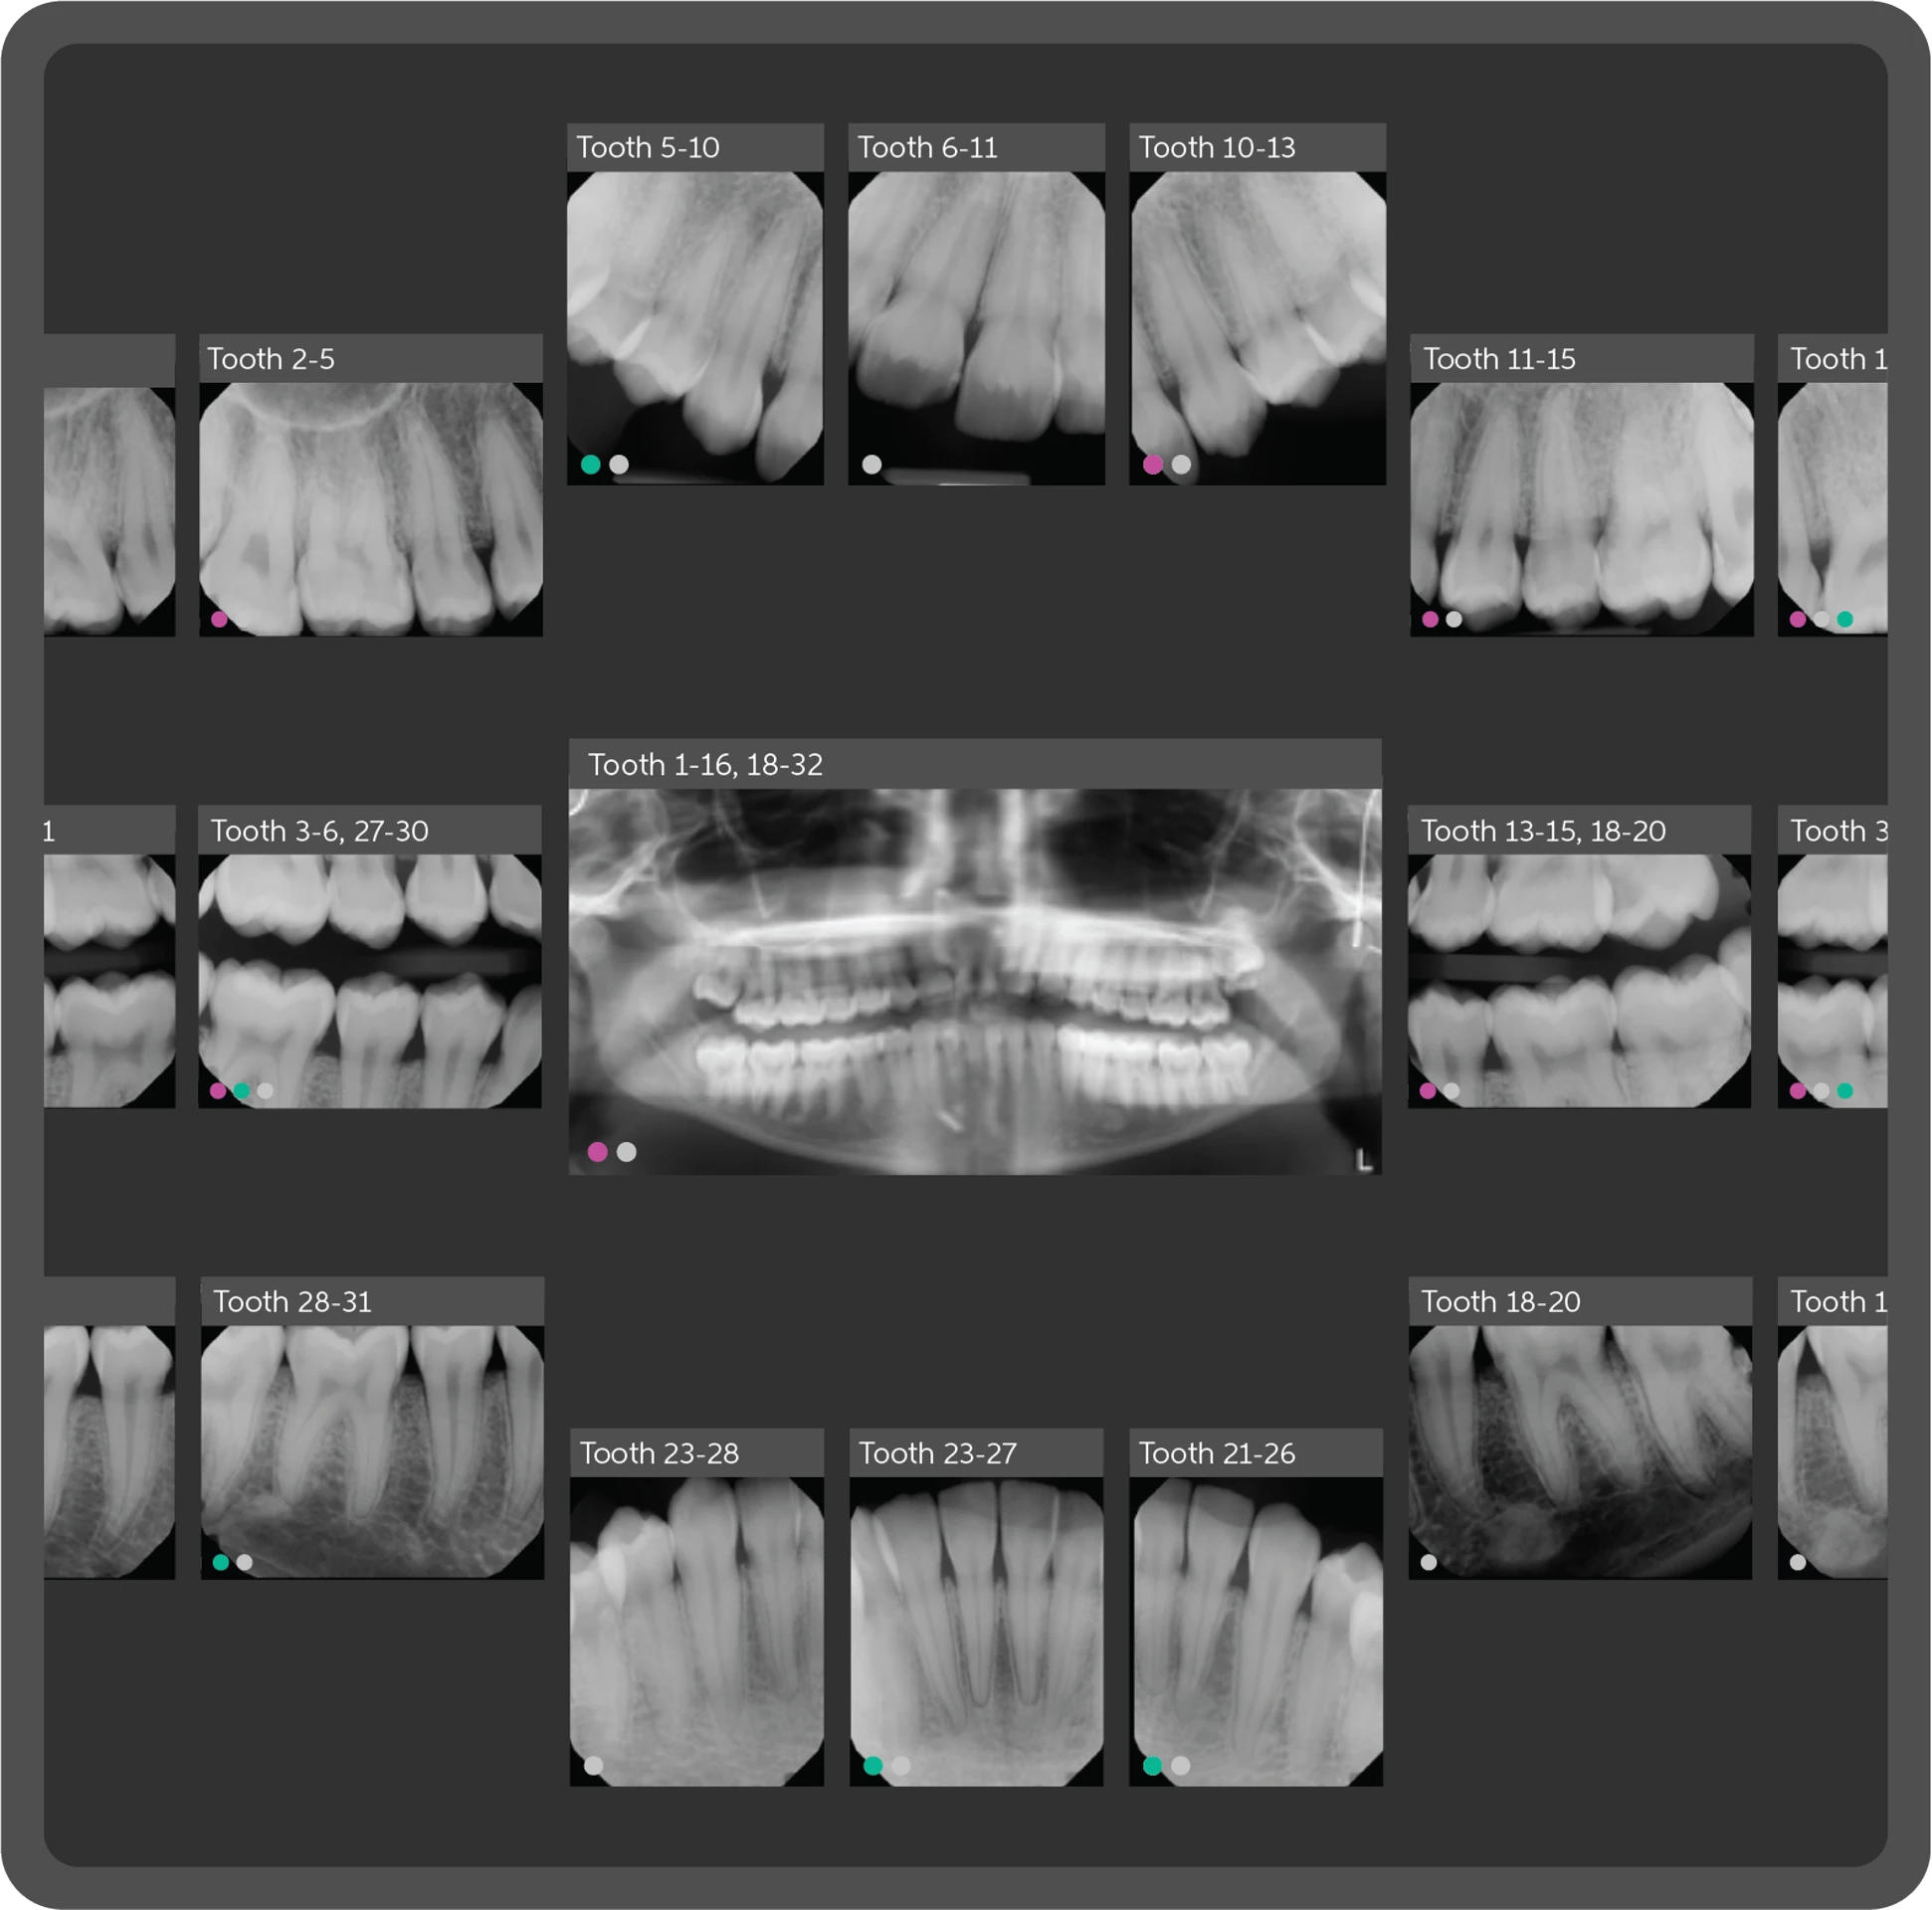

Pearl Dental AI is a cutting-edge artificial intelligence platform that acts as a second set of eyes, analyzing your X-rays with remarkable precision. This advanced technology helps us identify potential concerns earlier, ensure more consistent diagnoses, and ultimately, provide you with even more accurate and effective treatment plans.